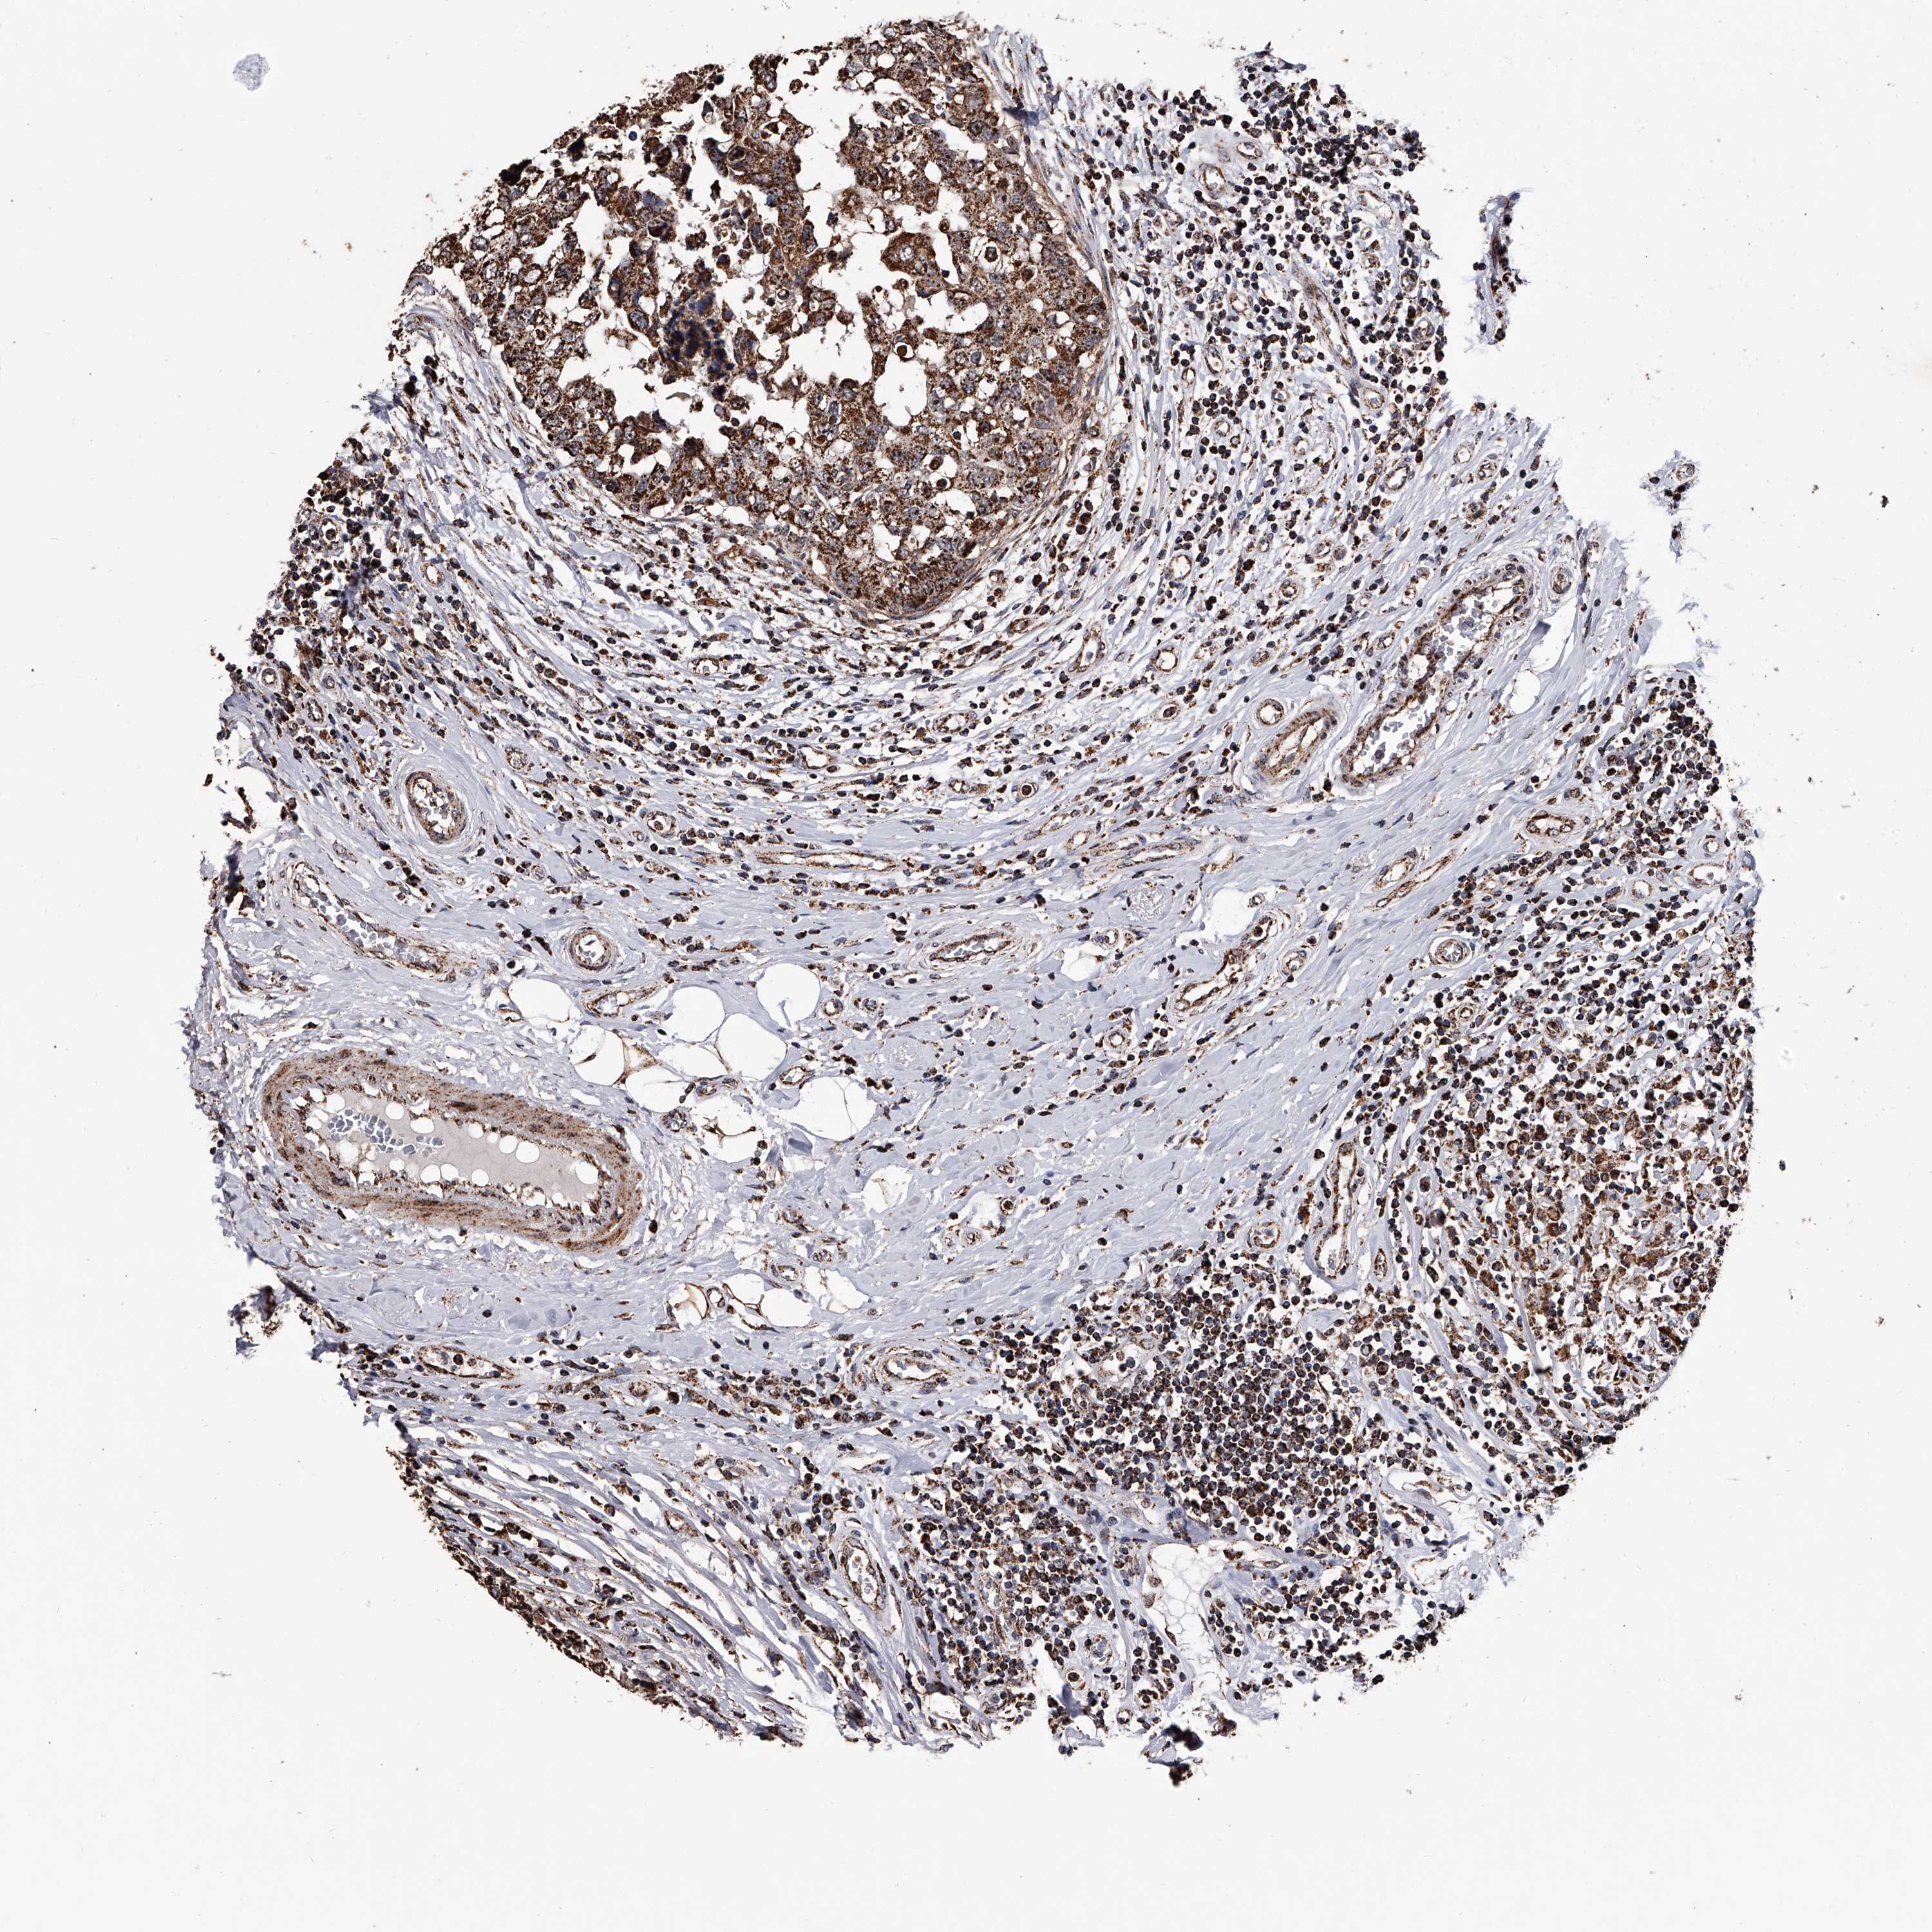

BRCA TCGA BRCA VALIDATION PROTEIN EXPRESSION